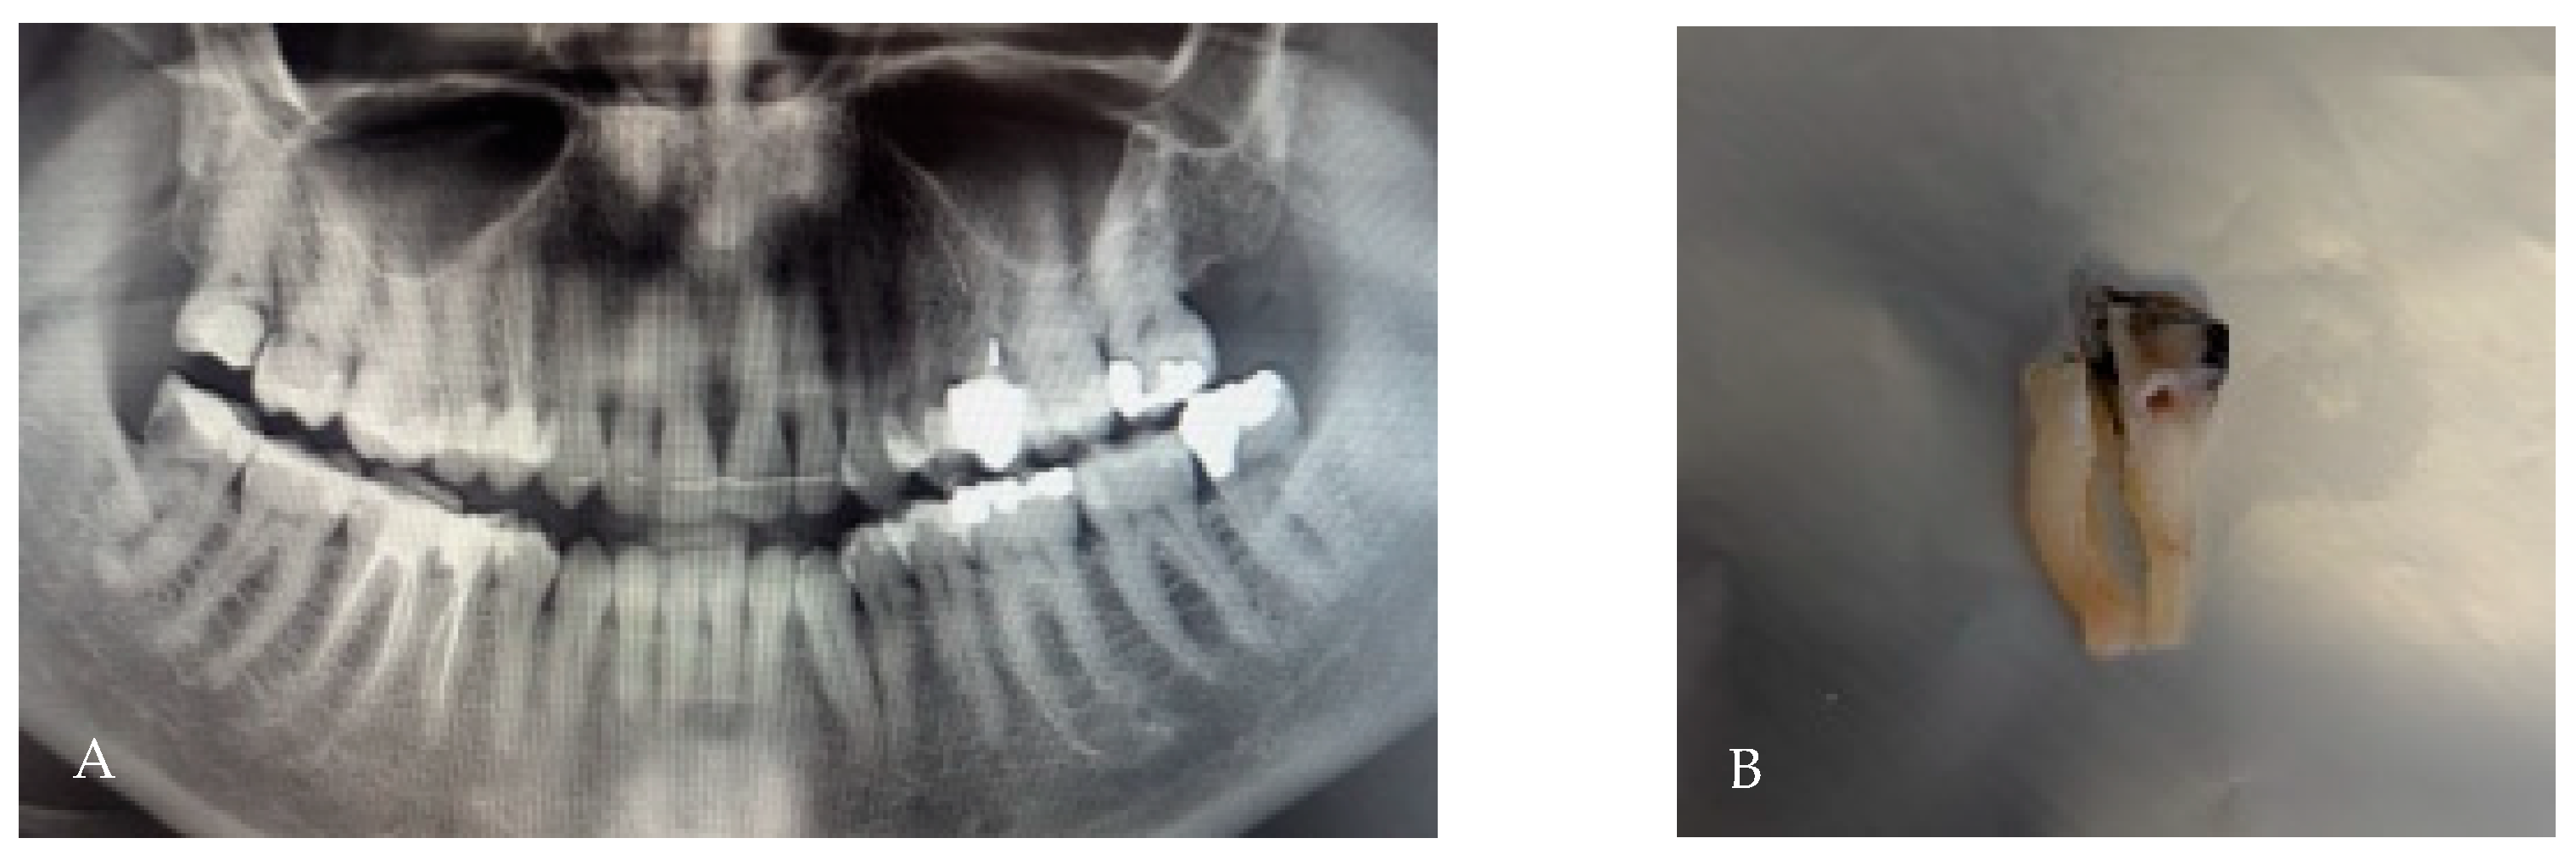

3.4. Taurodontism

- Hypotaurodont: mild displacement; furcation slightly apical, root length relatively preserved.

- Mesotaurodont: moderate displacement; larger pulp chamber, shorter roots.

- Hypertaurodont: severe displacement; very elongated pulp chamber, minimal root length, furcation close to the apex.

| Hypo-/Meso-/Hypertaurodont | Apical displacement of pulp floor; root shortening | Tooth-level 7–8%; individual 20–29% (mostly non-MTMs) | Reduced elevator purchase; require wider coronal troughing; control sectioning | [10,11] |